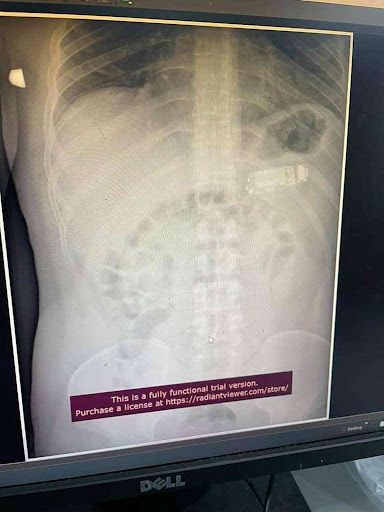

根据媒体《诗华日报》报道,早前一名来自科索沃的33岁男子称自己肚子痛前往医院就诊。想必一般的情况之下大家都会认为他小题大做,不过万万没想到,医生从X光照片中意外发现到,他把Nokia 3310直接吞下肚,让医生当场傻眼懵逼!

据悉,当时他的主诊医生表示男子的情况及其危险,因为手机不仅仅横向卡在他的胃里,同时还称Nokia 3310里的电池酸液随时都有可能外泄导致男子有生命危险。经过一番考量,医生才决定表示不开刀,选择通过内视镜的方式将手机分成三块夹出来。不过,这样也是有一定的风险的,他透露「在所有的零件中电池是最危险的,因为它可能随时会爆炸,我们尝试把异物从嘴巴里拉出来,如果失败的话再开刀」

从图片中可见,被取出来的Nokia 3310已经"被分尸",没办法恢复原来的样子以及功能。所幸的是整个手术极其成功,花了大约2个小时左右,男子没有任何生命危险,同时也没有出现并发症。当时,医生也将手术整个过程的影片放到了网络上,证实确有此事,同时也引发热议。至今,大家也无法理解为什么对方会将Nokia 3310吞下肚子,反正左看右看上看下看,能够确定从智力和大小来看都不是不小心的。